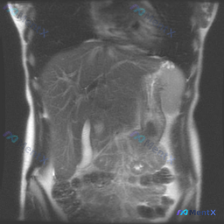

看到一份腹部MRI的影像分析,最初的问题是关于“脾脏病变”,但看完整个片子,觉得这远不止是脾脏的问题。整理了一下思路,和大家分享。 先看影像里的核心发现 这是一份腹部MRI-T2序列冠状位的影像: 1. 肝脏:形态不对,边缘是波浪状/结节状的(提示肝硬化);肝实质里有很多树枝状的高信号,是扩张的肝内...

整理到一份腹部MRI的影像分析资料,有点意思——用户最初的疑问是“这张图能看到脊柱侧弯吗”,但读下来发现,真正可能需要紧急处理的问题不在脊柱,而在脾脏。 先不说结论,先放关键影像表现: 1. 肝脏、胆道、胰腺、双肾(除右肾位置稍低)未见明显重大异常; 2. 脾脏明显增大,下极到腰椎中下段,实质内弥漫...